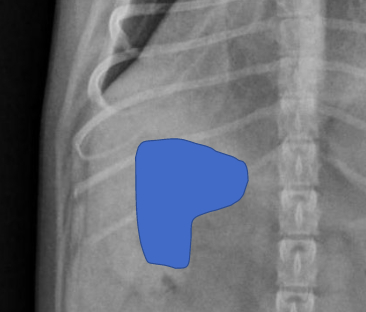

what is going on here bruh??

there is a mineralized adrenal mass. on the VD the mass is seen just left to the spine, and on the lateral, you can see a crescent shape opacity adjacent to the left kidney.